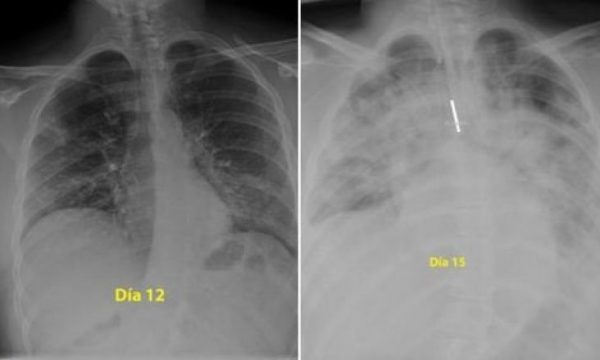

Për ata që besojnë se nuk preken dhe vazhdojnë të dalin në park pa zbatuar urdhrat për të ndenjur në shtëpi, ju ftojmë t’i shikoni mushkëritë e një djali 28-vjeçar të para me rreze X. Mushkëritë janë të zeza, ndërsa e bardhë është pneumonia ose lëngu i infeksionit që më pas bllokon frymëmarrjen. Pamjet janë publikuar nga një mjek në Spanjë, i quajtur Donni.

Agravimi i virusit është shumë i shpejtë dhe nga dita e 12 në të 15 shihet se mushkëritë e pacientit janë mbushur plot me lëngun e infeksionit.